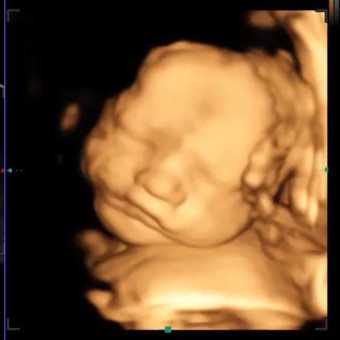

Jasper Rowe Humphreys

Alexandra Humphreys & Kasey Gaar-Humphreys

Hockley, TX

June 16, 2026

Thank you for helping us prepare for Jasper! We can’t wait to hold him in our arms.